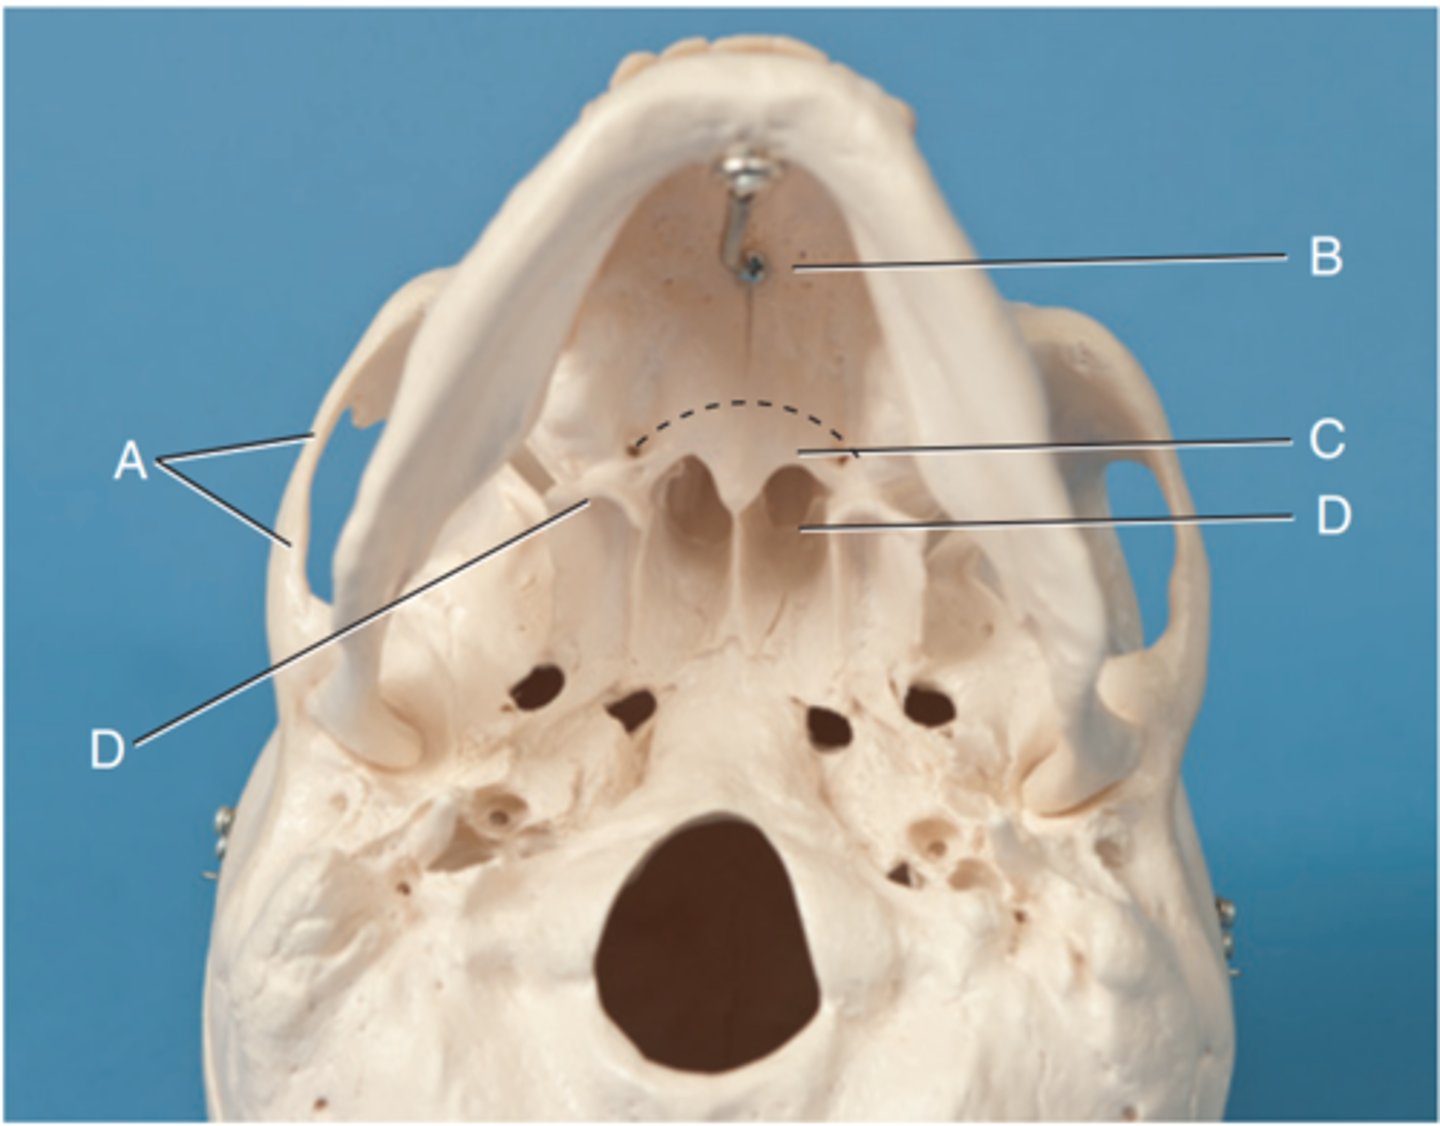

Label A

Posterior clinoid processes

Label B

Petrous ridge or petrous pyramid

Label C

Parietal bone

Label D

Occipital bone

Label E

Foramen magnum

Label F